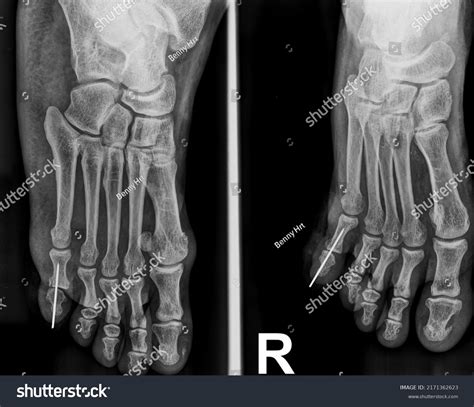

Okay, before we get into the nitty-gritty of ICD-10 codes, let’s quickly review the common foot bones and fracture types . The foot is a complex structure composed of 26 bones, divided into three main sections: the forefoot, midfoot, and hindfoot. The forefoot consists of the metatarsals and phalanges (toes), the midfoot includes the cuneiforms, navicular, and cuboid bones, and the hindfoot is made up of the talus and calcaneus (heel bone). Fractures in any of these bones can be quite painful and debilitating, affecting mobility and quality of life. Common types of foot fractures include metatarsal fractures, which are often seen in athletes or individuals who engage in high-impact activities. These fractures can occur due to direct trauma, overuse, or stress. Phalangeal fractures, or toe fractures, are also common and can result from stubbing the toe or dropping a heavy object on the foot. Midfoot fractures, such as those involving the navicular or cuneiform bones, are less frequent but can be more complex and may require surgical intervention.

Hindfoot fractures, particularly calcaneal fractures, are often caused by high-energy injuries like falls from a height or motor vehicle accidents. These fractures can be severe and may involve significant soft tissue damage. Another important type of foot fracture is a stress fracture, which is a small crack in the bone that develops over time due to repetitive stress or overuse. Stress fractures are commonly seen in runners, dancers, and military personnel. They typically occur in the metatarsals but can also affect other bones in the foot. When classifying foot fractures, it’s important to consider several factors, including the location of the fracture, the type of fracture (e.g., transverse, oblique, spiral, comminuted), and whether the fracture is open or closed. An open fracture, also known as a compound fracture, involves a break in the skin that exposes the bone to the outside environment, increasing the risk of infection. A closed fracture, on the other hand, does not involve a break in the skin. Additionally, fractures can be displaced, meaning the bone fragments are misaligned, or non-displaced, meaning the bone fragments are still in their normal alignment. Understanding these different types of foot fractures and the specific bones involved is crucial for accurate diagnosis and treatment planning. It also lays the groundwork for correctly assigning the appropriate ICD-10 codes, which we’ll delve into next.

Now, let’s get into the details about specific ICD-10 codes for foot fractures . This is where things get really interesting! The ICD-10 coding system provides a wide range of codes to classify different types of foot fractures, taking into account the specific bone involved, the nature of the fracture, and whether it’s an initial encounter, subsequent encounter, or sequela. Let’s start with some common examples. For a fracture of the calcaneus (heel bone), you might encounter codes like S92.001A for a fracture of the right calcaneus, initial encounter for closed fracture, or S92.002A for a fracture of the left calcaneus, initial encounter for closed fracture. If the fracture is open, the codes would be different, reflecting the increased risk of infection and the need for more intensive treatment.

Moving on to metatarsal fractures, the ICD-10 codes become even more specific. For example, S92.301A represents a fracture of the first metatarsal bone of the right foot, initial encounter for closed fracture, while S92.302A would indicate the same fracture in the left foot. The codes differentiate between fractures of each of the five metatarsal bones, allowing for precise documentation. Phalangeal fractures, or toe fractures, also have their own set of ICD-10 codes. A fracture of the great toe, for instance, might be coded as S92.401A for the right foot or S92.402A for the left foot. For fractures of the other toes, the codes would specify which toe is affected, such as S92.511A for a fracture of the second toe of the right foot. In addition to specifying the bone and location of the fracture, ICD-10 codes also indicate the encounter type. The initial encounter (indicated by the letter A) is used for the first time the patient receives treatment for the fracture. Subsequent encounters (indicated by the letter D) are used for follow-up visits, such as when the patient is receiving ongoing care or undergoing rehabilitation. Sequela (indicated by the letter S) is used for complications or conditions that arise as a direct result of the fracture, such as chronic pain or deformity. To ensure accurate coding, it’s essential to consult the ICD-10 coding manual and pay close attention to the documentation provided by the healthcare provider. The manual provides detailed instructions and guidelines for assigning the correct codes, taking into account all relevant factors. Remember, accurate ICD-10 coding is crucial for proper billing, reimbursement, and data tracking, so it’s worth taking the time to get it right.